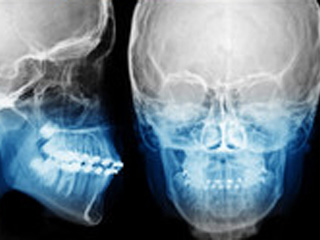

ライフ歯科・矯正歯科では、審美矯正の本質的治療を実践しています。咬合理論に基づいた「歯列」「咬合」「運動力学」の3つのアプローチで持続できる歯並びの美しさを提案し、機能性と審美性の両面を満たした矯正治療を行います。